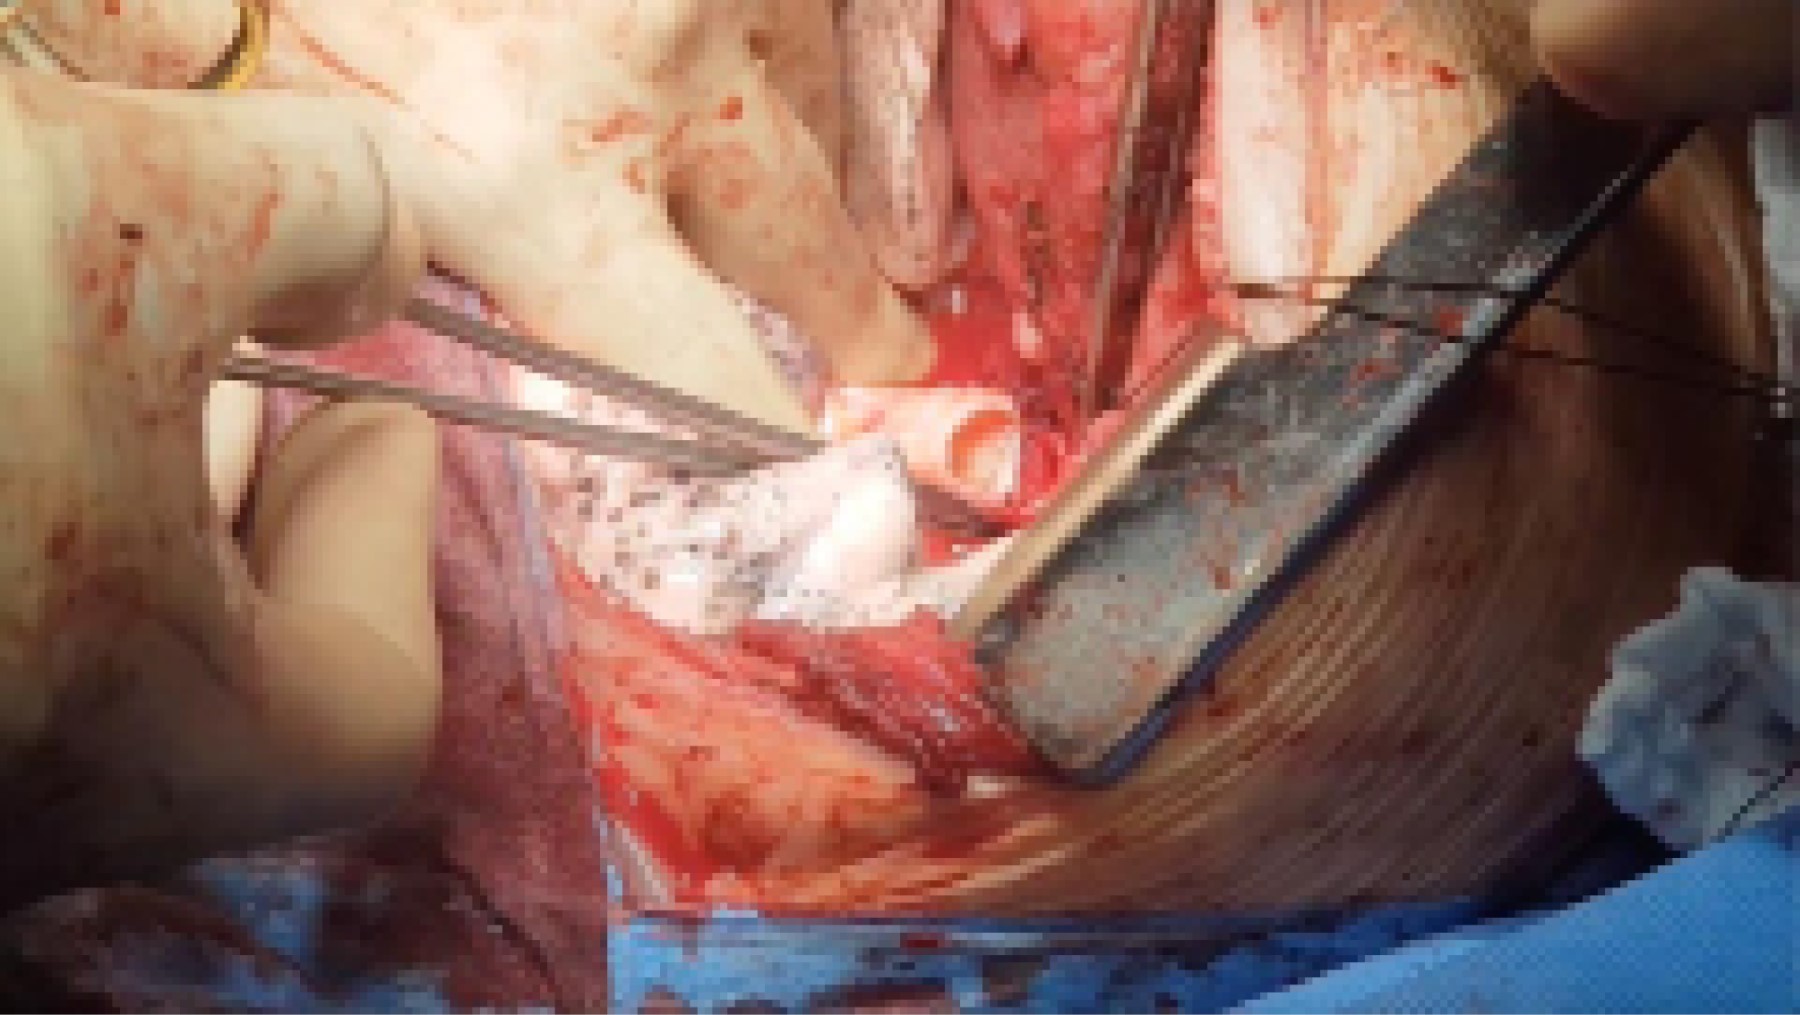

Para el implante pulmonar se realizó la anastomosis bronquial término-terminal con monofilamento absorbible del 3/0 mediante sutura continua tanto en pars membranosa como cartilaginosa (Figura 3). Las anastomosis vasculares fueron hechas con sutura continua, usándose polipropileno del 4/0 para la arteria pulmonar y 3/0 para la anastomosis auriculovenosa. Se colocaron dos drenajes pleurales tipo Blake del 24F en cada hemitórax, uno anterior y otro posterior. El tiempo de isquemia para ambos injertos fue inferior a las siete horas. El tiempo quirúrgico fue de seis horas y 40 minutos.

Figura 3